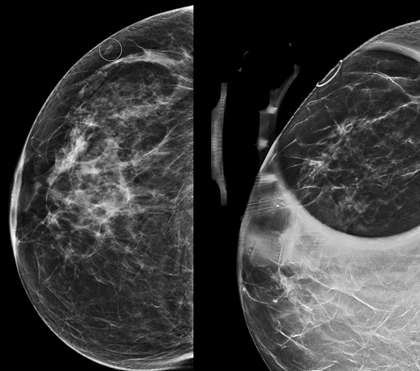

Aside from masses and architectural distortion, mammography is most useful for detecting breast calcifications. When calcifications project near the surface of the skin, dermal location must be considered and further worked up. The tangential view is used to prove the dermal location of a lesion by obtaining an image of the area of interest in tangent to the x-ray beam bringing into view the skin surface and the contrasting subdermal fatty tissue. The area of interest is localized with a skin BB marker through an alphanumeric grid guide. An imaginary line is then drawn from the BB marker towards the nipple. The tangential view is then obtained by rotating the C-arm so that the image receptor is parallel to the imaginary line.

Tomosynthesis can also be used for demonstrating dermal location of a lesion. In tomosynthesis, images obtained from multiple angles of a stationary compressed breast are reconstructed into series of thin 1-3 mm slices that span from the compression paddle to the beam detector (3). Skin lesions can then be identified by the superficial location of the reconstructed slice on which they are in focus.